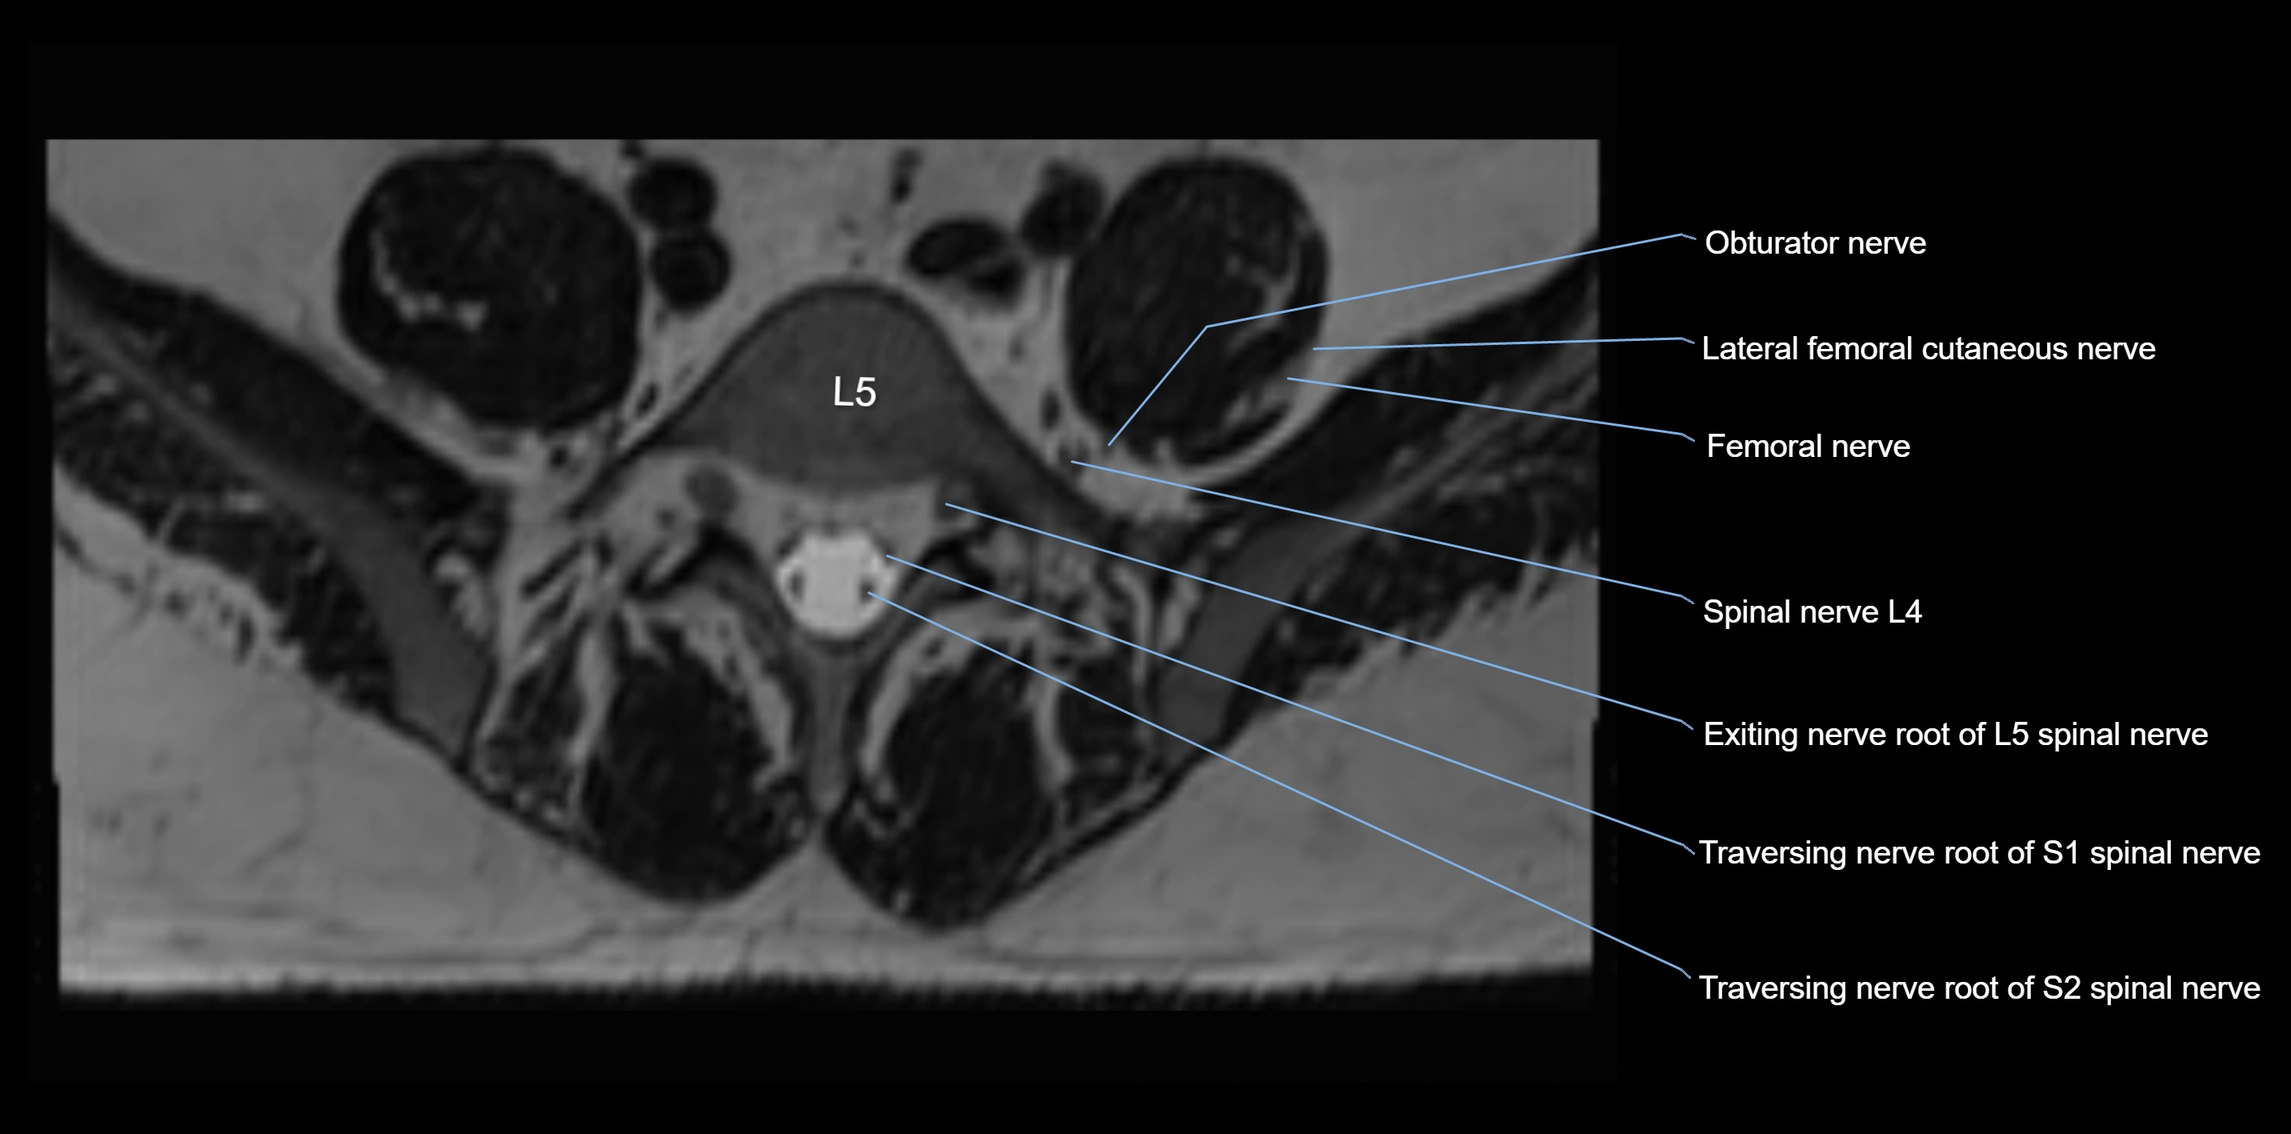

MRI Appearance

T1-weighted images:

• Nerve appears as a very thin low-to-intermediate signal intensity structure

• Surrounded by bright fat, aiding visualization

T2-weighted images:

• Nerve shows intermediate to mildly hyperintense signal compared to muscle

• Pathological involvement appears brighter

STIR (Short Tau Inversion Recovery):

• Normal nerve appears dark

• Inflamed or entrapped nerve appears bright hyperintense

T1 Fat-Sat Post-Contrast:

• Normal nerve enhances minimally

• Pathologic nerve (neuritis, entrapment, tumor infiltration) shows focal or diffuse enhancement

3D T2 SPACE / CISS:

• Nerve appears intermediate to mildly hyperintense compared to muscle

• Surrounded by bright fat or CSF, improving visualization

• Best sequence for mapping small pelvic nerves such as the anococcygeal

MRI image

image